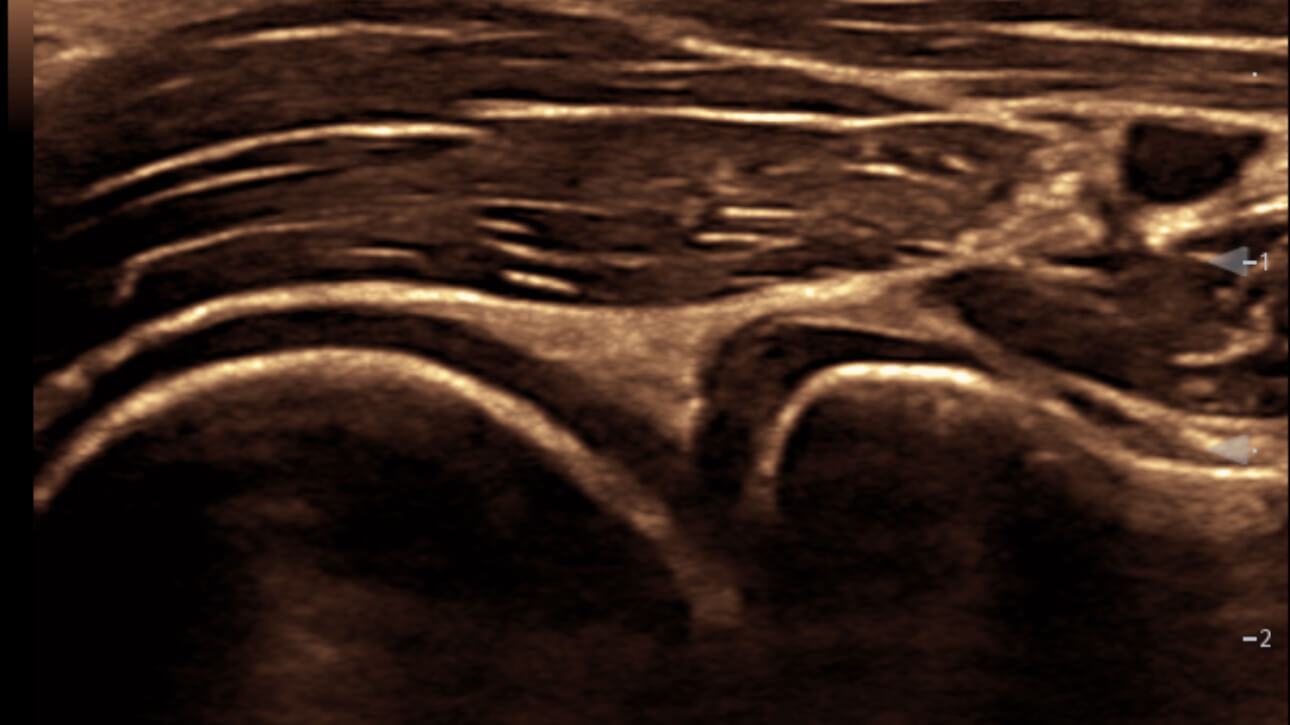

eSpacial Navi??and iNeedle+TM?ensure safe needling solution. Up to 20MHz ultra-high frequency linear transducer can visualize the finest nerves and fibers with extremely high resolution. Seamless monitor with full touch screen and exclusive clean-lock function ensure efficient cleaning and disinfection. The multiple modality design enables the TE5 to easily handle a wide range of medical scenarios.

Based on smart track of vessels, it can automatically optimize Color/Power and PW spectrum to reduce repetitive, time-consuming steps and simplify the vascular exam workflow:

- Real-time and automatically optimize Color box position & angle

- Real-time and automatically optimize PW sample volume position & angle & size